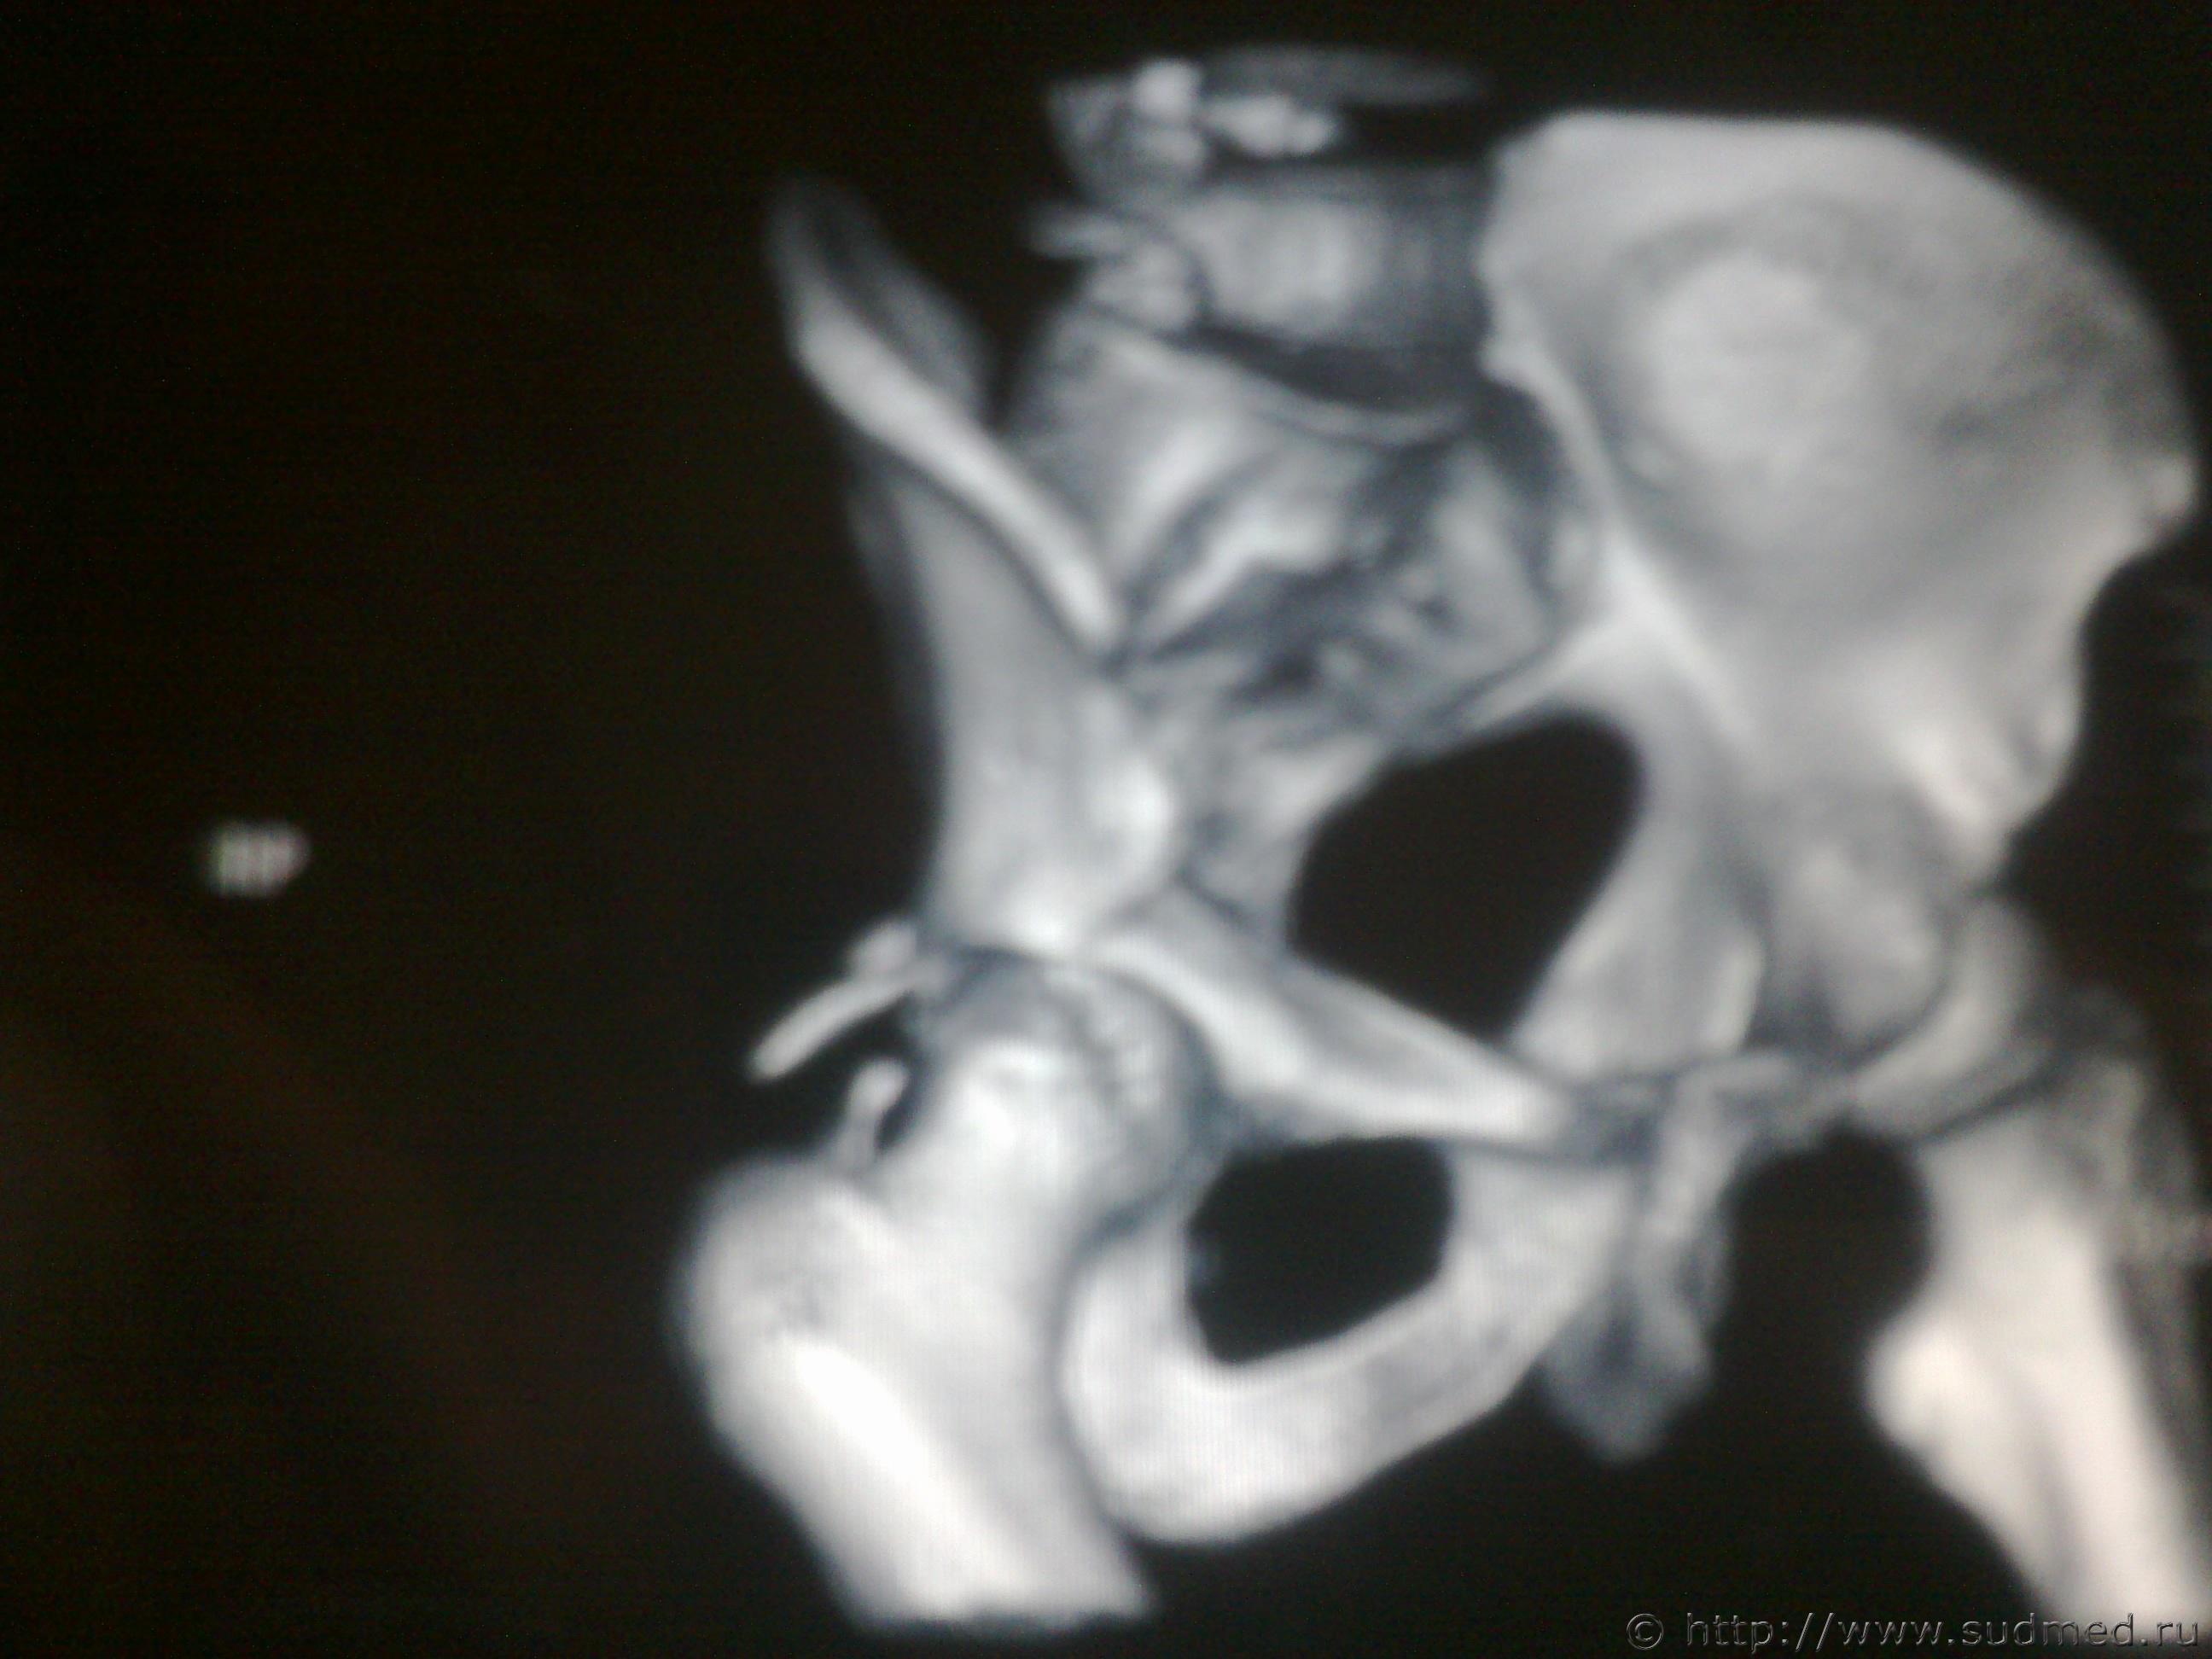

На основании этих снимков можно сделать заключение о вреде здоровья?

Судебная медицина - Прикрепленное изображение Судебная медицина - Прикрепленное изображение

1. Вертлужная впадина сломана - факт.

2. Костные отломки ее несколько смещены .

Следовательно - тяжкий вред (пункт 6.11.4. )

Совсем другое дело.

Видно хорошо.

Смещение отломков в области вертлужной впадины несомненное. Видно хорошо. Тяжкий вред. Без вариантов.